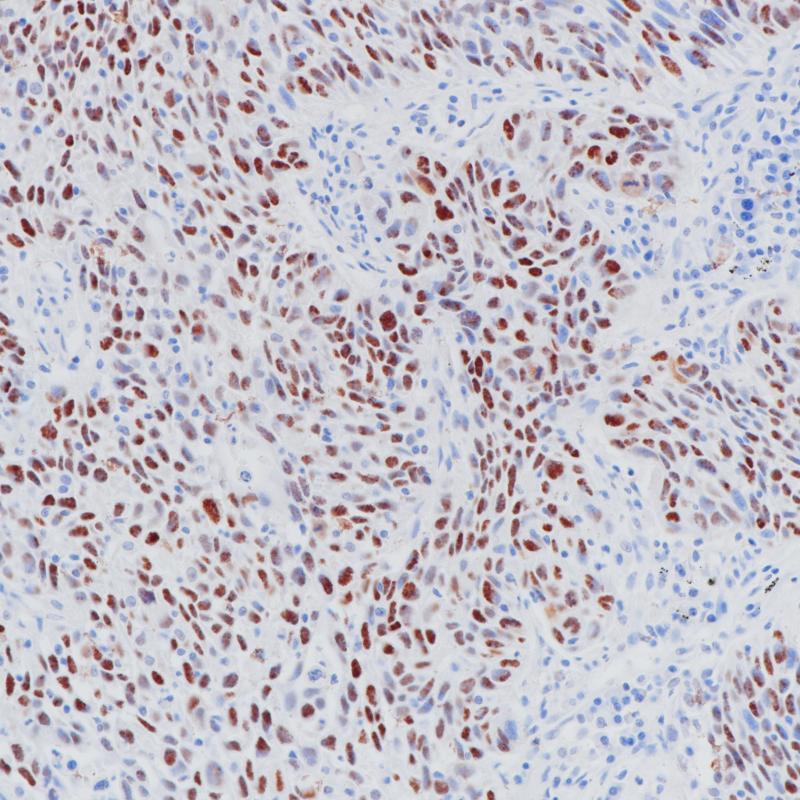

雌激素受体(ER)属于核受体超家族的类固醇受体,由553个氨基酸组成。雌激素受体分子具有三个结构域,即DNA结合中央结构域,C末端的激素结合结构域和N末端的转录激活结构域。ER参与女性性激素的调节功能,主要是17(E2),在一些目标组织的生长、分化和功能方面,如女性和男性生殖道,乳腺,骨骼和心血管系统。ER α存在于正常乳腺和子宫内膜组织的上皮细胞的细胞核,以及乳腺癌的亚型中。其次, ER α可作为一个肿瘤标志物,与抗孕酮受体的抗体组合,可用于腺癌的分类。

阳性对照

乳腺癌

亚细胞定位

细胞核